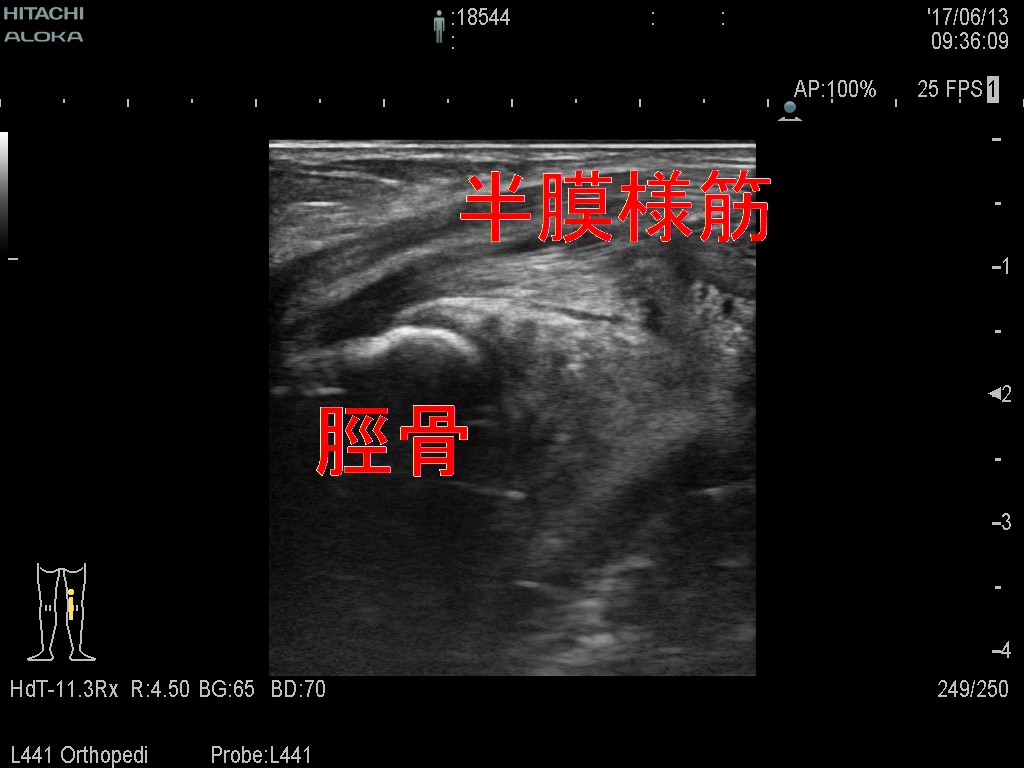

そして関節水腫やベーカーシストの原因になる半膜様筋

少量の水腫が半膜様筋周囲に認められた症例のリリース